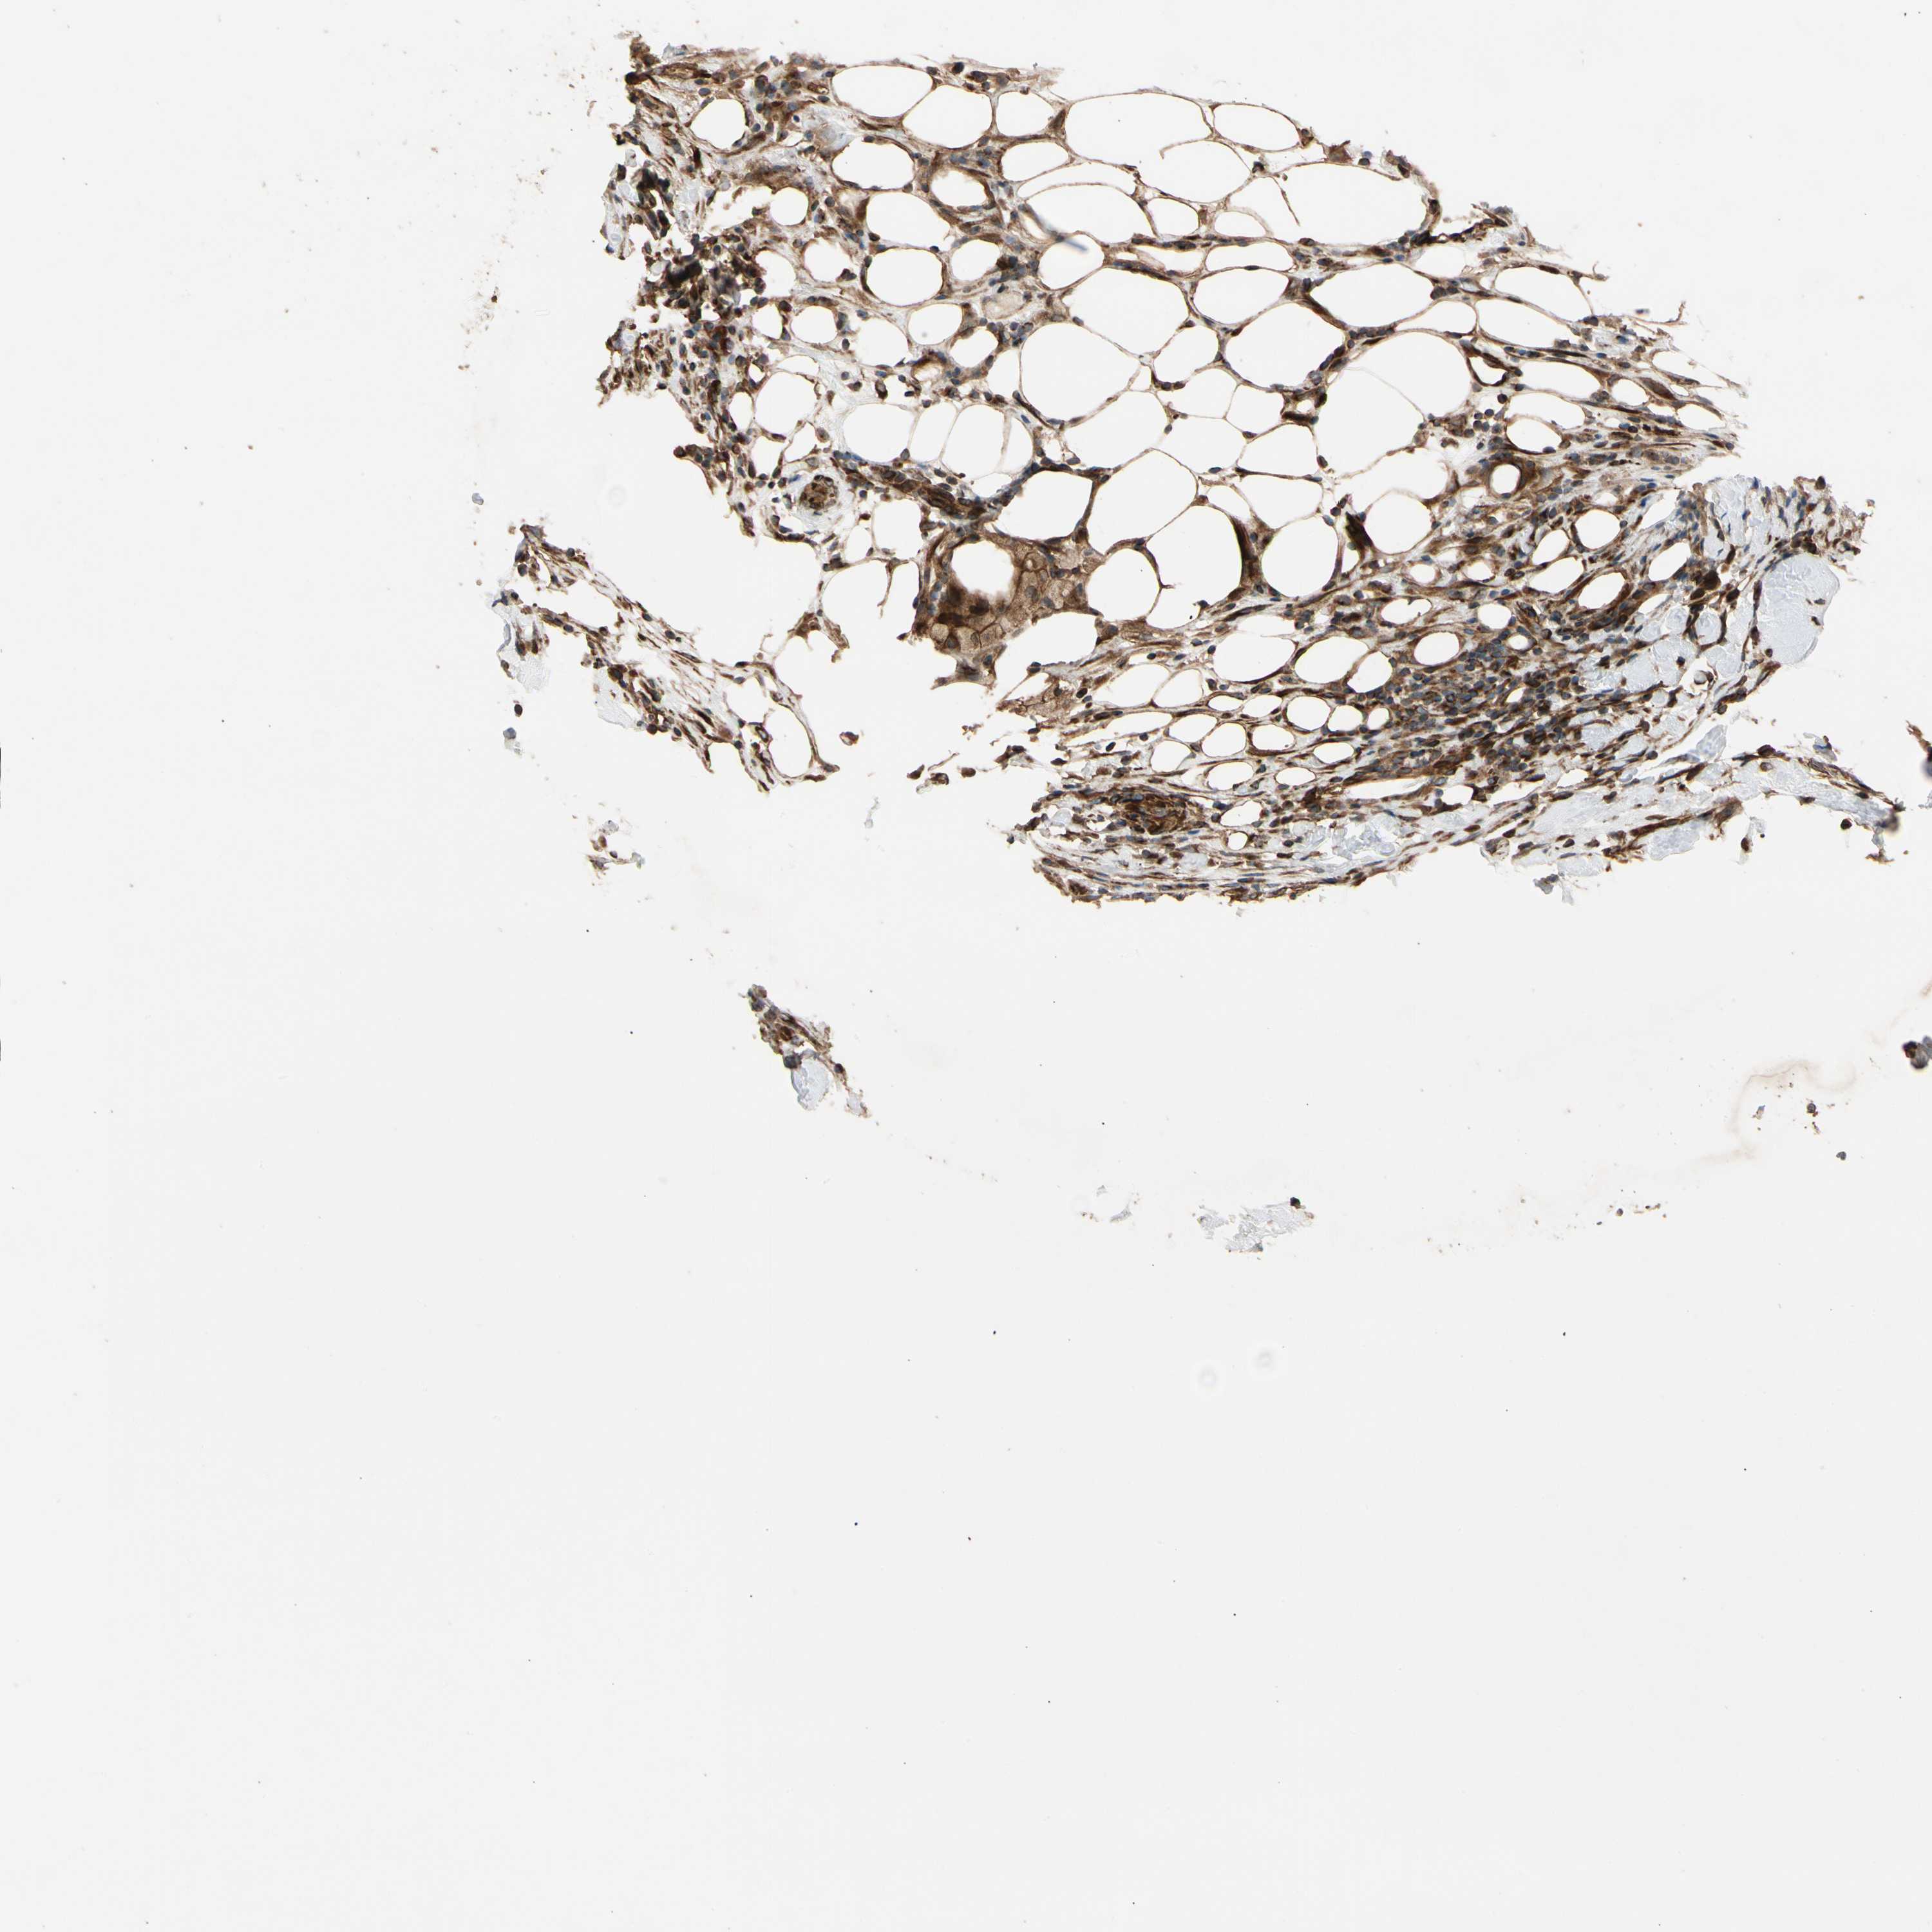

CANCER BREAST CANCER Show tissue menu

BRCA TCGA BRCA VALIDATION PROTEIN EXPRESSION